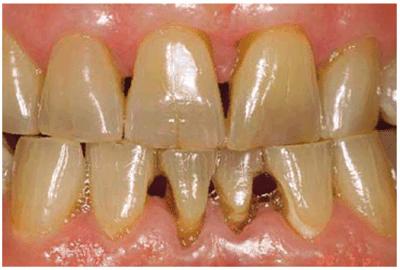

months of nightly treatment (Figures 16-18A, and 16-18B).48 Tetracycline

staining may take anywhere from 2 to 12 months of nightly treatment.49

Figure 16-18A: Years of pipe smoking have caused the extrinsic nicotine stain to become intrinsic.

Figure 16-18B: Whitening, using at-home treatment of 10% carbamide peroxide in a custom-fitted tray, was necessary to remove the stubborn nicotine stains.